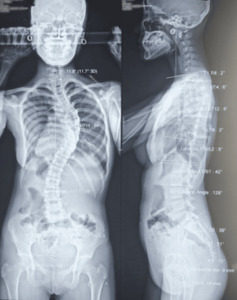

Diagnostic imaging played a crucial role in evaluating the severity of the patient’s scoliosis. Preoperative X-rays, obtained using EOS imaging, revealed a thoracic Cobb angle of 64° and a lumbar Cobb angle of 39°, indicating a severe degree of spinal curvature [Figure 2]. These findings confirmed the diagnosis of adolescent idiopathic scoliosis (AIS), characterized by a pronounced thoracic curvature. AIS is a common condition in adolescents, defined as an idiopathic lateral curvature of the spine that develops during the growth period.8

The postoperative management of this patient involved close monitoring in the intensive care unit (ICU) during the first 24 hours following surgery. Pain management was a critical component to mitigate potential adverse events and was effectively addressed with analgesics. Follow-up radiographic assessments demonstrated a satisfactory correction of the spinal deformity, with the thoracic Cobb angle reduced to approximately 15 degrees and the lumbar Cobb angle to 10 degrees [Figures 3-4].

Postoperative radiologic evaluation confirmed the efficacy of the surgical treatment, with significant improvement observed in the thoracic and lumbar spine. The thoracic Cobb angle was reduced to 15 degrees, and the lumbar Cobb angle to 10 degrees. These changes, based on the criteria used, represented favorable corrections of the spinal curvature.